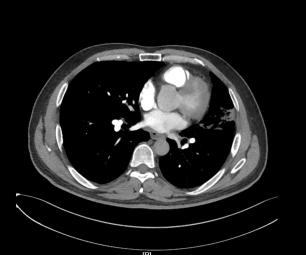

▎肺部增强CT(图片如下)

2.右上肺尖段少许慢性炎症;

3.纵隔多发肿大淋巴结,拟反应性增生,建议随诊;

4.拟左上肺多发体-肺动脉分流形成;

5.支气管动脉重建示左侧支气管动脉稍增粗。

反复阅读肺部CT并与影像科同事联系,患者肺部CT提示间质水肿、左肺上静脉显示不清,结合患者存在射频消融史,需要考虑肺静脉狭窄引起的咯血。

送入猪尾巴导管至双肺动脉造影示,左肺动脉造影见左上肺外周血管未显影,未见左上肺静脉回流,左下肺动脉显影良好,左下肺静脉回流尚好。

右肺动脉造影见右上肺动脉显影好,右上肺静脉回流尚可,进入左心房入处狭窄,约30%,右下肺动脉显影好,右下肺静脉回流尚可。超选LA1支造影显示左上肺静脉回流至左房入口处明显狭窄,约90%,左肺静脉回流处血管团造影剂渗出。

其中肺静脉增强CT检查及血管三维重建诊断PSV效果明显,该例患者我院首先完善了肺部动脉增强CT,影像科医生在报告中未报左肺静脉异常,我们反复阅读片子发现左肺静脉异常,从而进一步行右心导管、左心导管、肺动脉造影术,以此明确诊断;而使用心脏彩超诊断PVS中需警惕因操作者主观因素导致的诊断遗漏,注意加强与辅助科室之间的提醒。